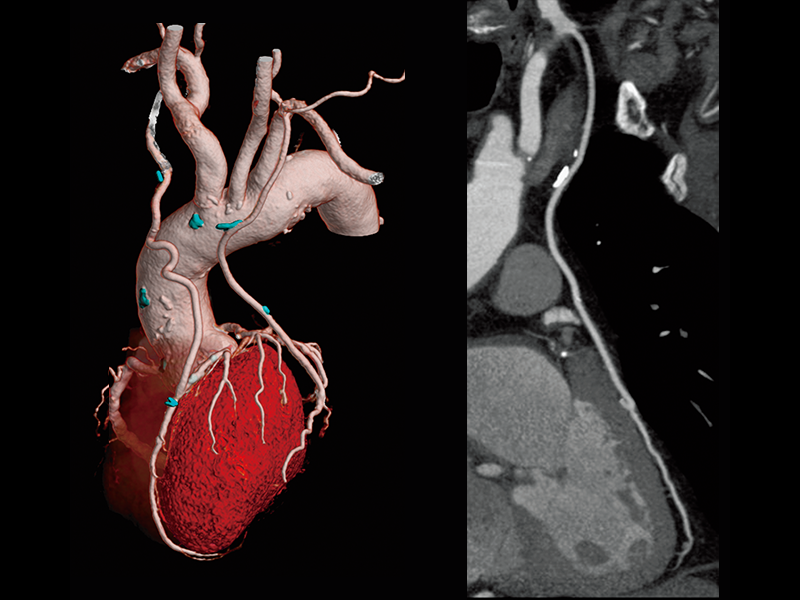

Follow-up after CABG

Follow-up after LAD stenting

High-speed imaging(180 mm/sec)

Renal cell carcinoma(80 kV)

Abdominal aortic occlusion